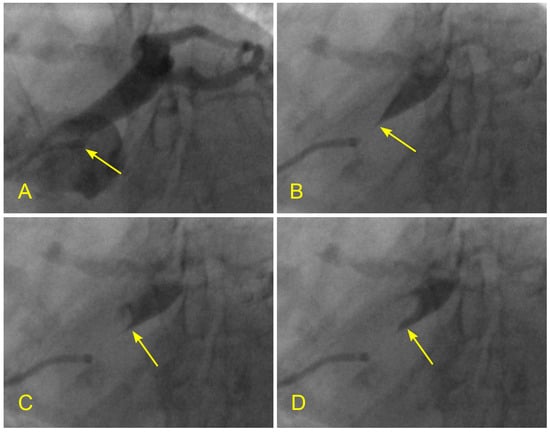

Figure 15.

(A–F) Reverse flow in distal right coronary artery. This is a series of six sequential images separated by 6 milliseconds each (15 images per second). (A) The blood, in white, moves forward to the distal right coronary artery (RCA) (arrow) past the origin of the posterior descending artery (PDA) (arrowhead). (B) The blood (white) is now clearly distal to the origin of the PDA (arrow), while the contrast at the origin of the PDA stays stagnant and homogenously black (arrowhead). (C) Flow reversal. At the beginning of systole, at the distal RCA, the contrast reverses its direction and flows back past the origin of the PDA (arrow). (D) At the distal RCA, the blood (in white) pushes back the contrast (arrow) in the antegrade direction. The flow reversal is short-lived. (E,F) At the distal RCA, the blood, in white, moves forward as usual (arrow). If the reversed flow had been strong and lasted longer, more damage could have been inflicted on the endothelium and could have triggered the atherosclerotic cascade.